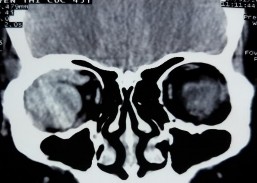

Bệnh nhân nữ, 44 tuổi, MP: đau nhức, lồi mắt, phù kết mạc Chẩn đoán MP: Ung thư biểu mô dạng tuyến nang

Bệnh nhân phù kết mạc khoảng 1 tuần trước vào viện (A). Bệnh nhân có tiền sử cắt u hốc mắt cách vào viện 16 năm, không điều trị bổ sung gì. Hình ảnh cắt lớp vi tính hốc mắt có khối u vùng tuyến lệ tăng giảm tỉ trọng hỗn hợp, bờ không đều, kích thước 26 x 40 mm, đẩy cơ thẳng trên, không quan sát được cơ thẳng ngoài, phá hủy xương (C, D). X-quang ngực đã di căn phổi. Kết quả giải phẫu bệnh là ung thư biểu mô dạng tuyến nang (E: HE x 40, F: HE x 100). Điều trị phẫu thuật cắt bỏ u phối hợp cắt bỏ xương + hóa trị + xạ trị (B).